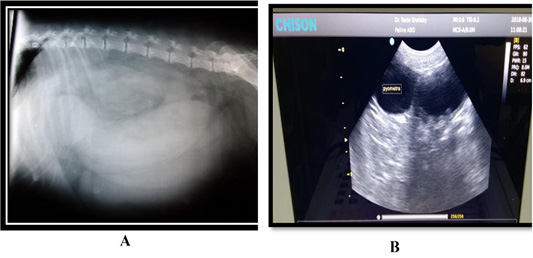

(A) Radiograph for pyometra in queen showing a sausage-like fluid filled tubular organ; (B) B- mode ultrasound sagittal scan at the level of right flank region of a 3- years- old Persian cat suffered from closed pyometra. Notice hyperechoic thickened wall with intralumenal trapiculi and anechoic content of the right uterine horn.